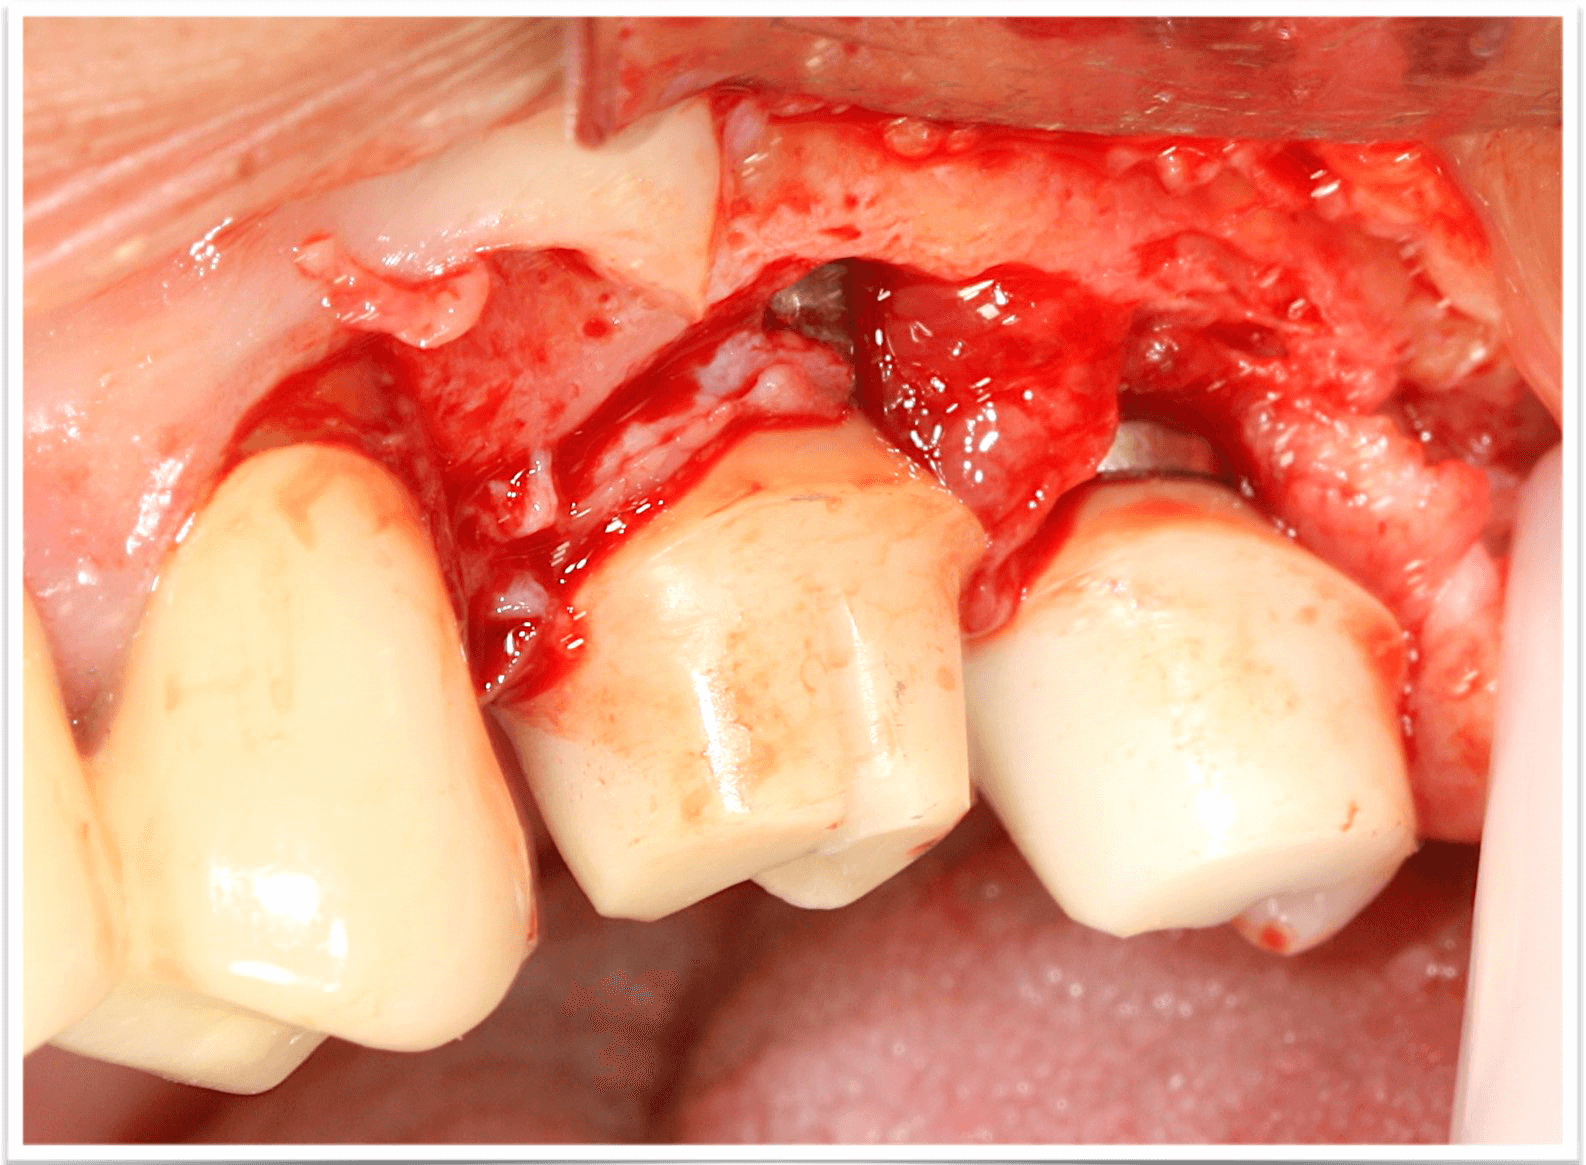

Устранение эстетических осложнений в области имплантатов. Преимущества методики VISTA

Лекция посвящена современным подходам к коррекции эстетических недостатков в области мягких тканей вокруг зубных имплантатов. Будет рассмотрена методика VISTA (Vertical Incision Subperiosteal Tunnel Access), как минимально инвазивный способ работы с мягкими тканями. Обсудим ключевые преимущества: снижение травматичности, высокую предсказуемость результатов и улучшение эстетики в зонах улыбки. Особое внимание уделим выбору донорских материалов, работе с сосудистой сетью и нюансам заживления. Лекция будет сопровождаться клиническими примерами и практическими рекомендациями для применения метода в повседневной практике.